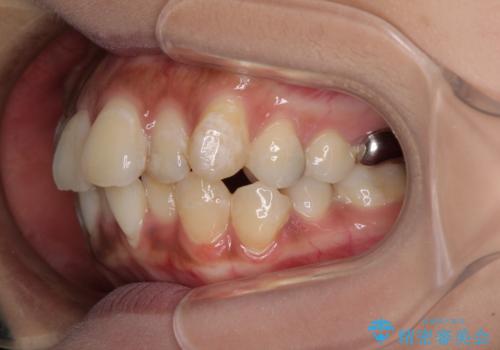

- 口元の閉じにくさを気にして来院された患者様です。

上下ともに歯列が前方に突出していたため、上下左右の第一小臼歯4本を抜去し、ワイヤー装置による矯正治療を行うこととしました。

舌の突出癖による影響もあったため、舌のトレーニングを並行して実施しました。

左下奥歯にむし歯が認められるため、矯正治療後にセラミックインレーにて修復治療を行うこととしました。